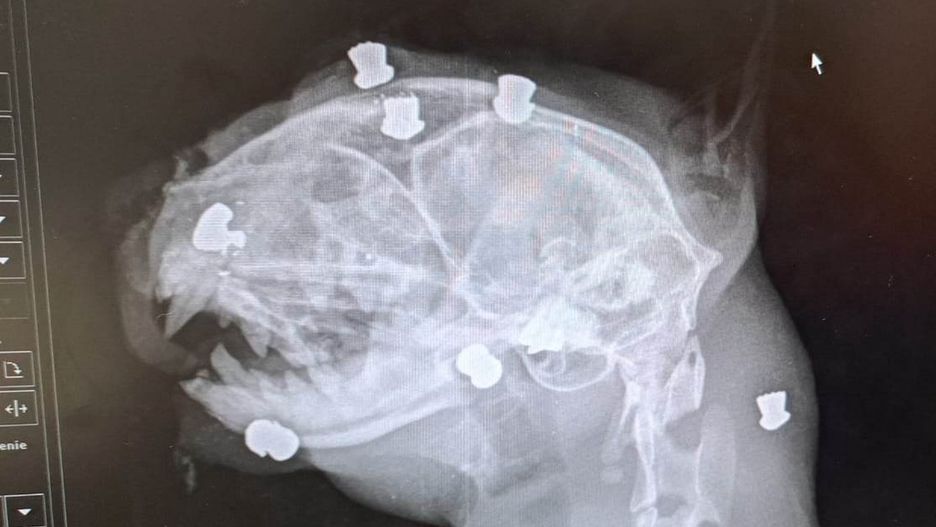

Pracownicy kliniki weterynaryjnej nie mogli uwierzyć w to, co widzą na zdjęciu rentgenowskim bezdomnego kota znalezionego przy ulicy Grunwaldzkiej w Dębicy. Ślady śrutu w głowie kota świadczą, że ze zwierzęcia zrobiono sobie żywą tarczę.

Pierwsze oględziny wywołały łzy i wściekłość. Ten biedny schorowany kot był żywą tarczą strzelniczą. Ma mnóstwo śrutów w całym ciele - komentują pracownicy fundacji.

Gdy weterynarz zrobił prześwietlenie poranionej głowy zwierzęcia, okazało się, że znajduje się w niej drugie tyle śrutu.

Pracownicy fundacji zdjęcie rentgenowskie wrzucili do sieci. Pod nim napisali:

To, co widać, to czaszka kotka z ul. Grunwaldzkiej w Dębicy. Jego głowa, czaszka, całe ciało naszpikowane jest śrutami stożkowymi. Był tarczą strzelniczą. Ktoś prawdopodobnie go trzymał (lub przywiązał), a inny zwyrodnialec go okaleczał... Śruty są w czaszce, nosie, pyszczku, wszędzie. Gałka oczna do usunięcia, wyciek krwisty z nosa, być może uszkodzona zatoka nosowa (śrutem).